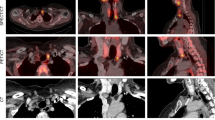

Left superior parathyroid gland depicted by 11C-methionine (patient 1, hypercalcaemic hyperparathyroidism; Table 1). Upper left, CT scan; upper right, 11C-methionine PET scan [SUV(parathyroid tissue/cervical soft tissue)=4.9]; lower left, 11C-methionine PET/CT fusion image

Among the 18 patients, high-resolution ultrasound identified two enlarged parathyroid glands in 11, three glands in six and four enlarged glands in one (Table 1). In ten of the 18 patients (55.5%), PET/CT demonstrated abnormal accumulation of 11C-methionine (one parathyroid gland in eight patients and two glands in two patients) (Table 1). Mean SUV(parathyroid tissue/cervical soft tissue) was 3.3 (range 2.1–4.9) and mean SUV(parathyroid tissue/thyroid tissue) was 2.5 (range 1.5–3.6). There was no significant difference in parathyroid gland 11C-methionine SUVs between the group with normal or low calcium levels and the group with hypercalcaemic hyperparathyroidism. It is of note that in patients with normo- or hypocalcaemic hyperparathyroidism, 11C-methionine PET/CT identified one abnormal gland in only three of ten patients (30%), while in the group with hypercalcaemic hyperparathyroidism, seven of eight patients (87.5%) had abnormal 11C-methionine PET/CT (p<0.01 by χ2 test). Of the latter seven patients, five had one abnormal gland (Figs. 1, 2) and two, two abnormal glands on PET/CT. The significant difference observed in the rate of detection of abnormal parathyroid glands at 11C-methionine PET/CT in the group of normo- or hypocalcaemic patients versus the group of hypercalcaemic patients might be explained by the fact that in hypercalcaemic patients, that is patients more likely to be affected by tertiary hyperparathyroidism, autonomous parathyroid glands could be biologically more active in trapping 11C-methionine. Further, in four of the ten patients (40%) with abnormal 11C-methionine PET/CT scans (all of whom had hypercalcaemic hyperparathyroidism), the largest parathyroid gland seen on high-resolution ultrasound did not demonstrate the highest 11C-methionine avidity. Comparisons of SUV with serum calcium and parathyroid hormone levels and parathyroid gland weight by regression analysis did not reveal statistically significant differences. No patient had co-existing thyroid nodules in the present series.

All patients were treated with subtotal parathyroidectomy. In the majority of patients the remnant parathyroid tissue was from the smallest of the parathyroid glands. All 11C-methionine-accumulating glands were resected, regardless of their size. Pathological evaluation of the resected parathyroid glands was consistent with glandular hyperplasia and there were no differences in the pathological findings between 11C-methionine-avid parathyroid glands and non-11C-methionine-avid glands.